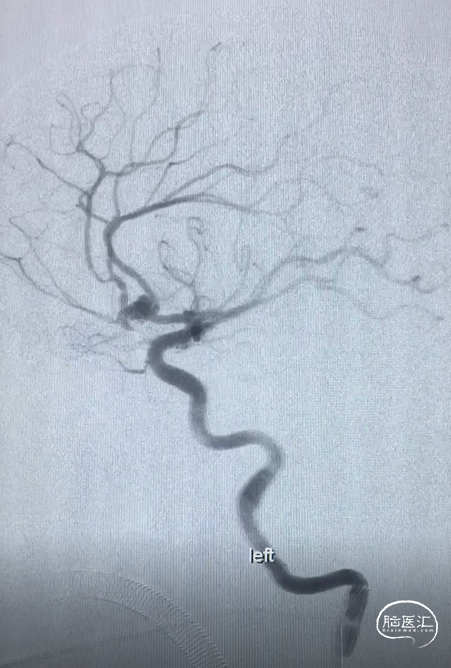

术前DSA:RCCA正侧位造影